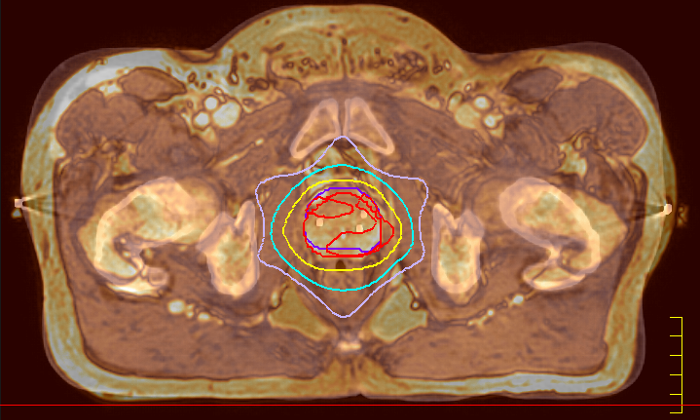

With its exceptional soft-tissue visualization capabilities and wide range of image contrasts, MRI has become a powerful tool to help more precisely define tumor boundaries. This is particularly important as it has been established that there is a high degree of uncertainty in target volume delineation, and it is even reported to represent the largest uncertainty in the entire radiotherapy process for most tumor sites**. Better visualization of the target area and nearby organs-at-risk is a key factor in enhancing target volume delineation. MRI’s expanding role also can be attributed to its functional imaging capabilities, which can inform both target characterization and treatment response.

With its superior soft tissue contrast compared to CT, MRI offers exquisite visualization of tumor boundaries and proximity to nearby critical structures.

The ability to tune contrasts can provide even more valuable information about tumor characteristics and tumor extent to facilitate enhanced delineation, and also provides possibilities for dose boosting strategies.

Innovative MR-only simulation helps you use MRI as the primary imaging modality for planning prostate cancer patients’ treatment, thereby eliminating tedious and error-prone CT-MR registration and simplifying workflows. Available as a plug-in extension to the Ingenia MR-RT platform, MR-only simulation provides high contrast anatomical MR images for target delineation and the density information for dose calculations typically provided by CT.